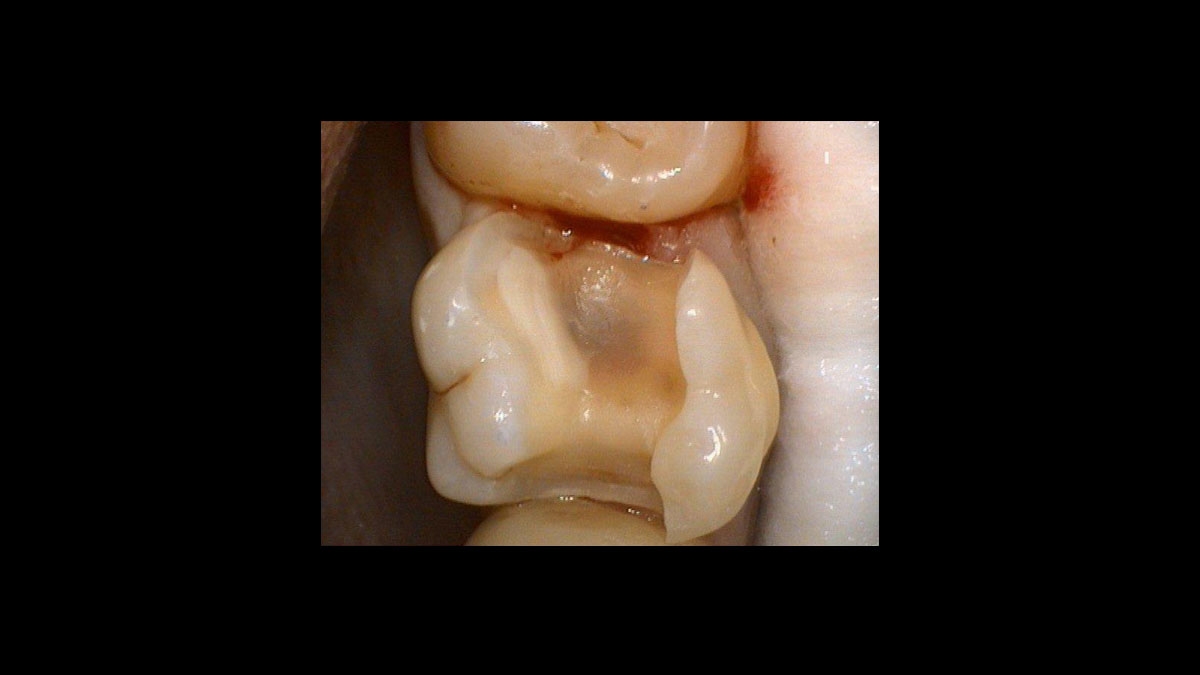

Tooth 16 after preparation

After the Hemostasis